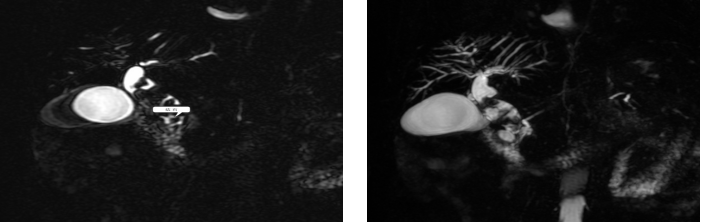

核磁共振下的胆总管结石影:

入院后查HS-CRP >5.0 mg/L、CRP. 65.40 mg/L。ALT 112.30 U/L、ALB 29.80 g/L、GLU 6.29 mmol/L、GGT 508.30 U/L、ALP 306.20 U/L、TBIL 108.90 umol/L、DBIL 68.00 umol/L,腹部CT(平扫,增强扫描):1、右肝内胆管、肝总管、胆总管多发结石并胆管炎,肝内外胆管、肝总管、胆总管扩张。2、胰腺炎。肝胆脾胰(平扫,MRCP):1、急性水肿性胰腺炎。2、右肝内胆管、肝总管及胆总管多发结石并梗阻,其上游胆道系统扩张。诊断为:1、急性胰腺炎(胆源性,轻度)2、右肝内胆管、肝总管、胆总管多发结石并胆管炎。患者病情逐步平稳,症状改善。胆总管结石不除随时可能加重患者病情并延缓患者恢复时间。